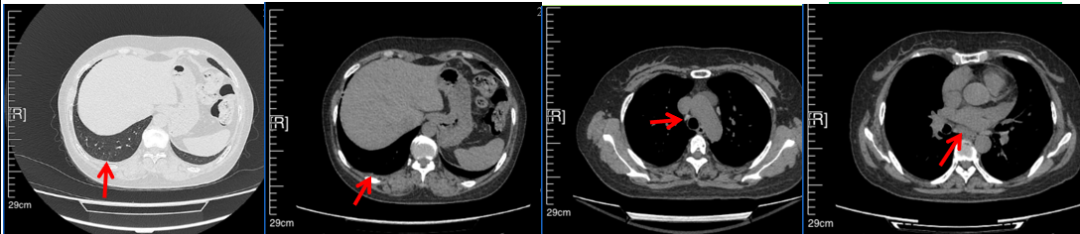

56岁,女性,无吸烟史饮酒史,既往体健。2023年02月患者体检发现肺占位性病变,胸部增强CT:右肺下叶后基底段结节;右侧锁骨上及纵隔内多发淋巴结肿大。PET-CT:右肺下叶周围型肺癌可能性大;1R、2L、3P、4R、4L及7组淋巴结转移可能性大。2023年02月就诊于本院胸外科行超声胃镜下纵隔肿物穿刺活检术,病理:结合免疫组化,符合肺腺癌。行NGS基因检测:EML4:exon20-ALK:exon20融合。PD-L1(克隆号22C3)TPS=55%。

临床诊断:右肺下叶恶性肿瘤cT1bN3M0,IIIB(第9版分期),纵隔淋巴结继发恶性肿瘤,锁骨上淋巴肿继发恶性肿瘤

治疗经过:2023年3月27日始行恩沙替尼靶向治疗至今,最佳疗效为PR,末次评效为维持PR。期间出现轻度肝功能异常(DILI 1级),对症处理后好转。截止目前PFS为26个月。

2023年2月20日基线检查

2024年6月复查PR(最佳疗效)